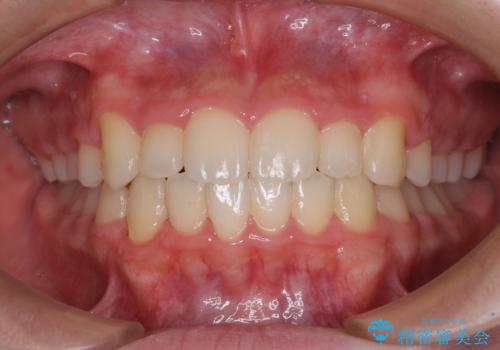

極端な上下前歯の開咬を改善 オープンバイトのインビザライン矯正

- 上下前歯の隙間を気にして来院された患者様です。

開咬の治療は、前歯を閉じるように動かすとともに、上下臼歯を圧下(骨内にめり込ませる)させることで進めて行きます。

インビザラインは臼歯の圧下を効果的に行えるため、インビザラインを用いて矯正治療を行うこととしました。

治療前に、いくらインビザライン矯正がオープンバイトを得意としているとは言え、さすがに限界があるだろうと思っておりましたが、前歯でレタスが噛めるまで改善することができました。

顔の印象も大きく変わり、患者様には大変満足していただきました。